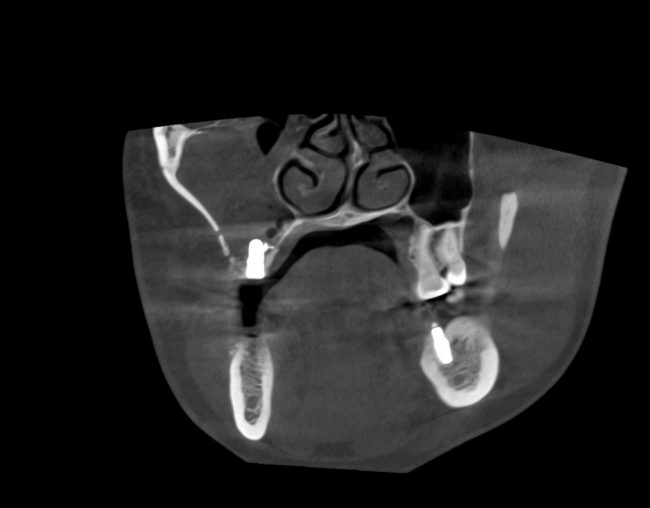

Первая операция — мы не можем сразу поставить имплантат из-за почти полного отсутствия кости между полостью рта и дном верхнечелюстной пазухи:

Через 3 месяца — вторая операция — установка имплантата в сформированный объем костной ткани: